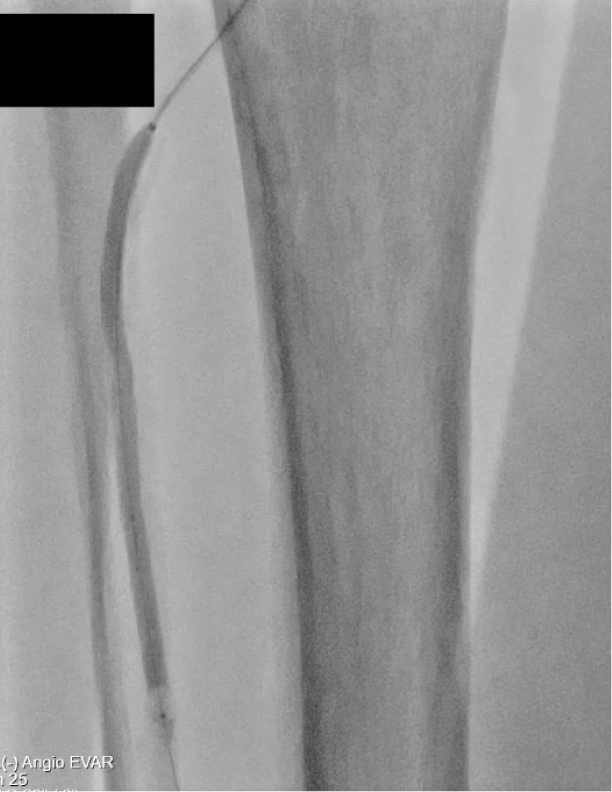

• Baseline Angio showing diffuse Anterior Tibial disease

Baseline Angio showing diffuse Anterior Tibial disease.